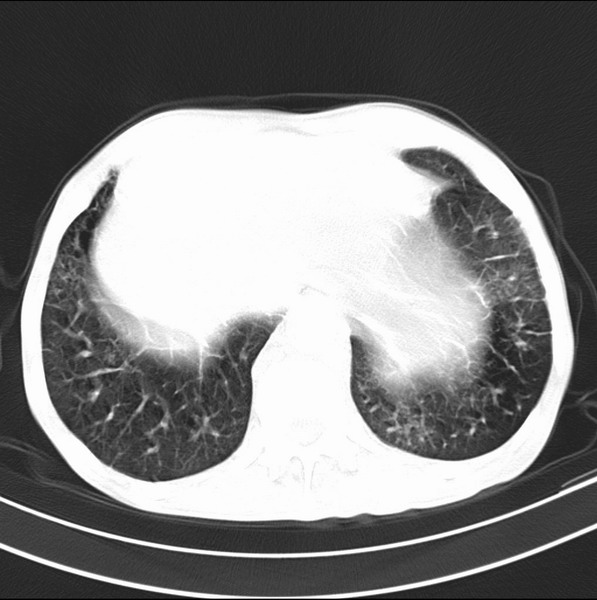

标题: CT19600:能否诊断为转移?

女、55

3年前盲肠癌、一年半前诊断膀胱癌,现在呼吸困难,临床考虑为肺转移

请问胸部ct如何诊断?能否排除淋巴管炎,纵隔窗没有问题。

炎性并间质纤维化

炎性并间质纤维化,请询问病史,如用过平阳霉素或其他化疗药.可能为药物引起的间质纤维化.